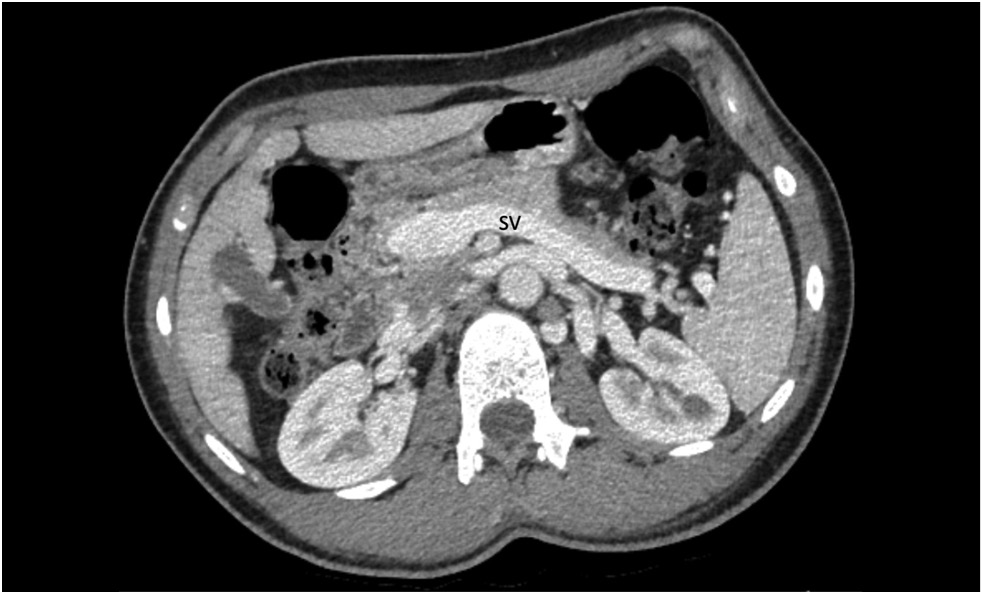

Abernethy malformation: A case report

Abstract

Congenital portosystemic shunts are rare congenital vascular malformations characterized by a partial or complete portal blood diversion into the systemic circulation. Congenital extrahepatic portosystemic shunts, known as Abernethy malformations, pose a diagnostic challenge due to their low incidence and clinical presentations.

A 15-year-old male with a history of chronic epigastric pain and nausea, high arterial blood pressure, recurrent nose bleeds, chest pain, dizziness, dyspnea, low exercise tolerance, hematochezia, and itching was diagnosed with Abernethy malformation type Ib. Imaging studies revealed a dilated portal vein conduit flowing into the inferior vena cava, bypassing the porta hepatis. Multiple liver nodules, heart chamber dilatation, myocardial hypertrophy, and pulmonary hypertension were also discovered. Following multidisciplinary panel meetings, liver transplantation was advised due to the severity of the patient’s symptoms and shunt anatomy.

Furthermore, diagnostic algorithms and other treatment options are discussed.

226-237